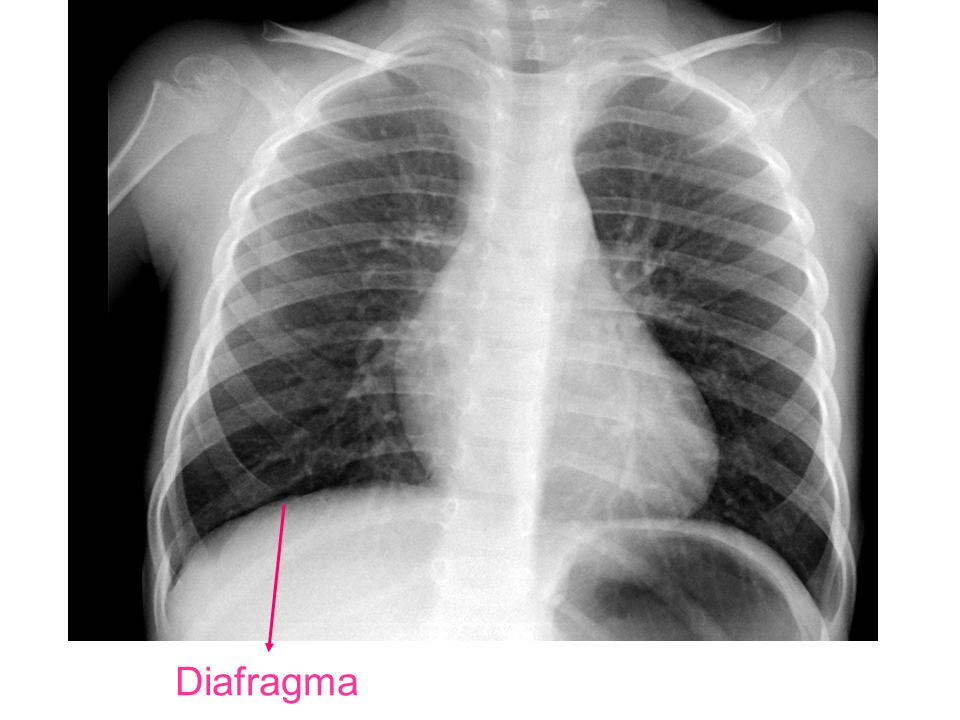

Para una adecuada lectura sistemática de la radiografía de tórax, debemos conocer la anatomía radiológica básica e identificar determinadas estructuras2.

• Diafragma